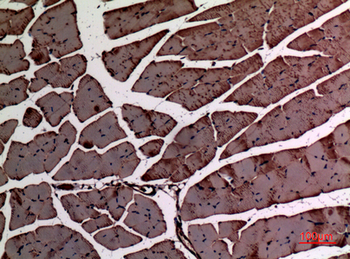

α-SMA Polyclonal Antibody

Catalog Number: orb1411650

| Catalog Number | orb1411650 |

|---|---|

| Category | Antibodies |

| Description | Rabbit polyclonal antibody to α-SMA. |

| Clonality | Polyclonal |

| Species/Host | Rabbit |

| Conjugation | Unconjugated |

| Reactivity | Human, Mouse, Rat |

| UniProt ID | P68133 |

| Tested applications | IHC-P, WB |

| Dilution range | WB: Western Blot: 1/500 - 1/2000. IHC-p: 1:100-300 ELISA: 1/20000. Not yet tested in other applications. |

| Storage | Maintain refrigerated at 2-8°C for up to 2 weeks. For long term storage store at -20°C in small aliquots to prevent freeze-thaw cycles |

| Alternative names | ACTA1; ACTA; Actin, alpha skeletal muscle; Alpha-a Read more... |

| Note | For research use only |